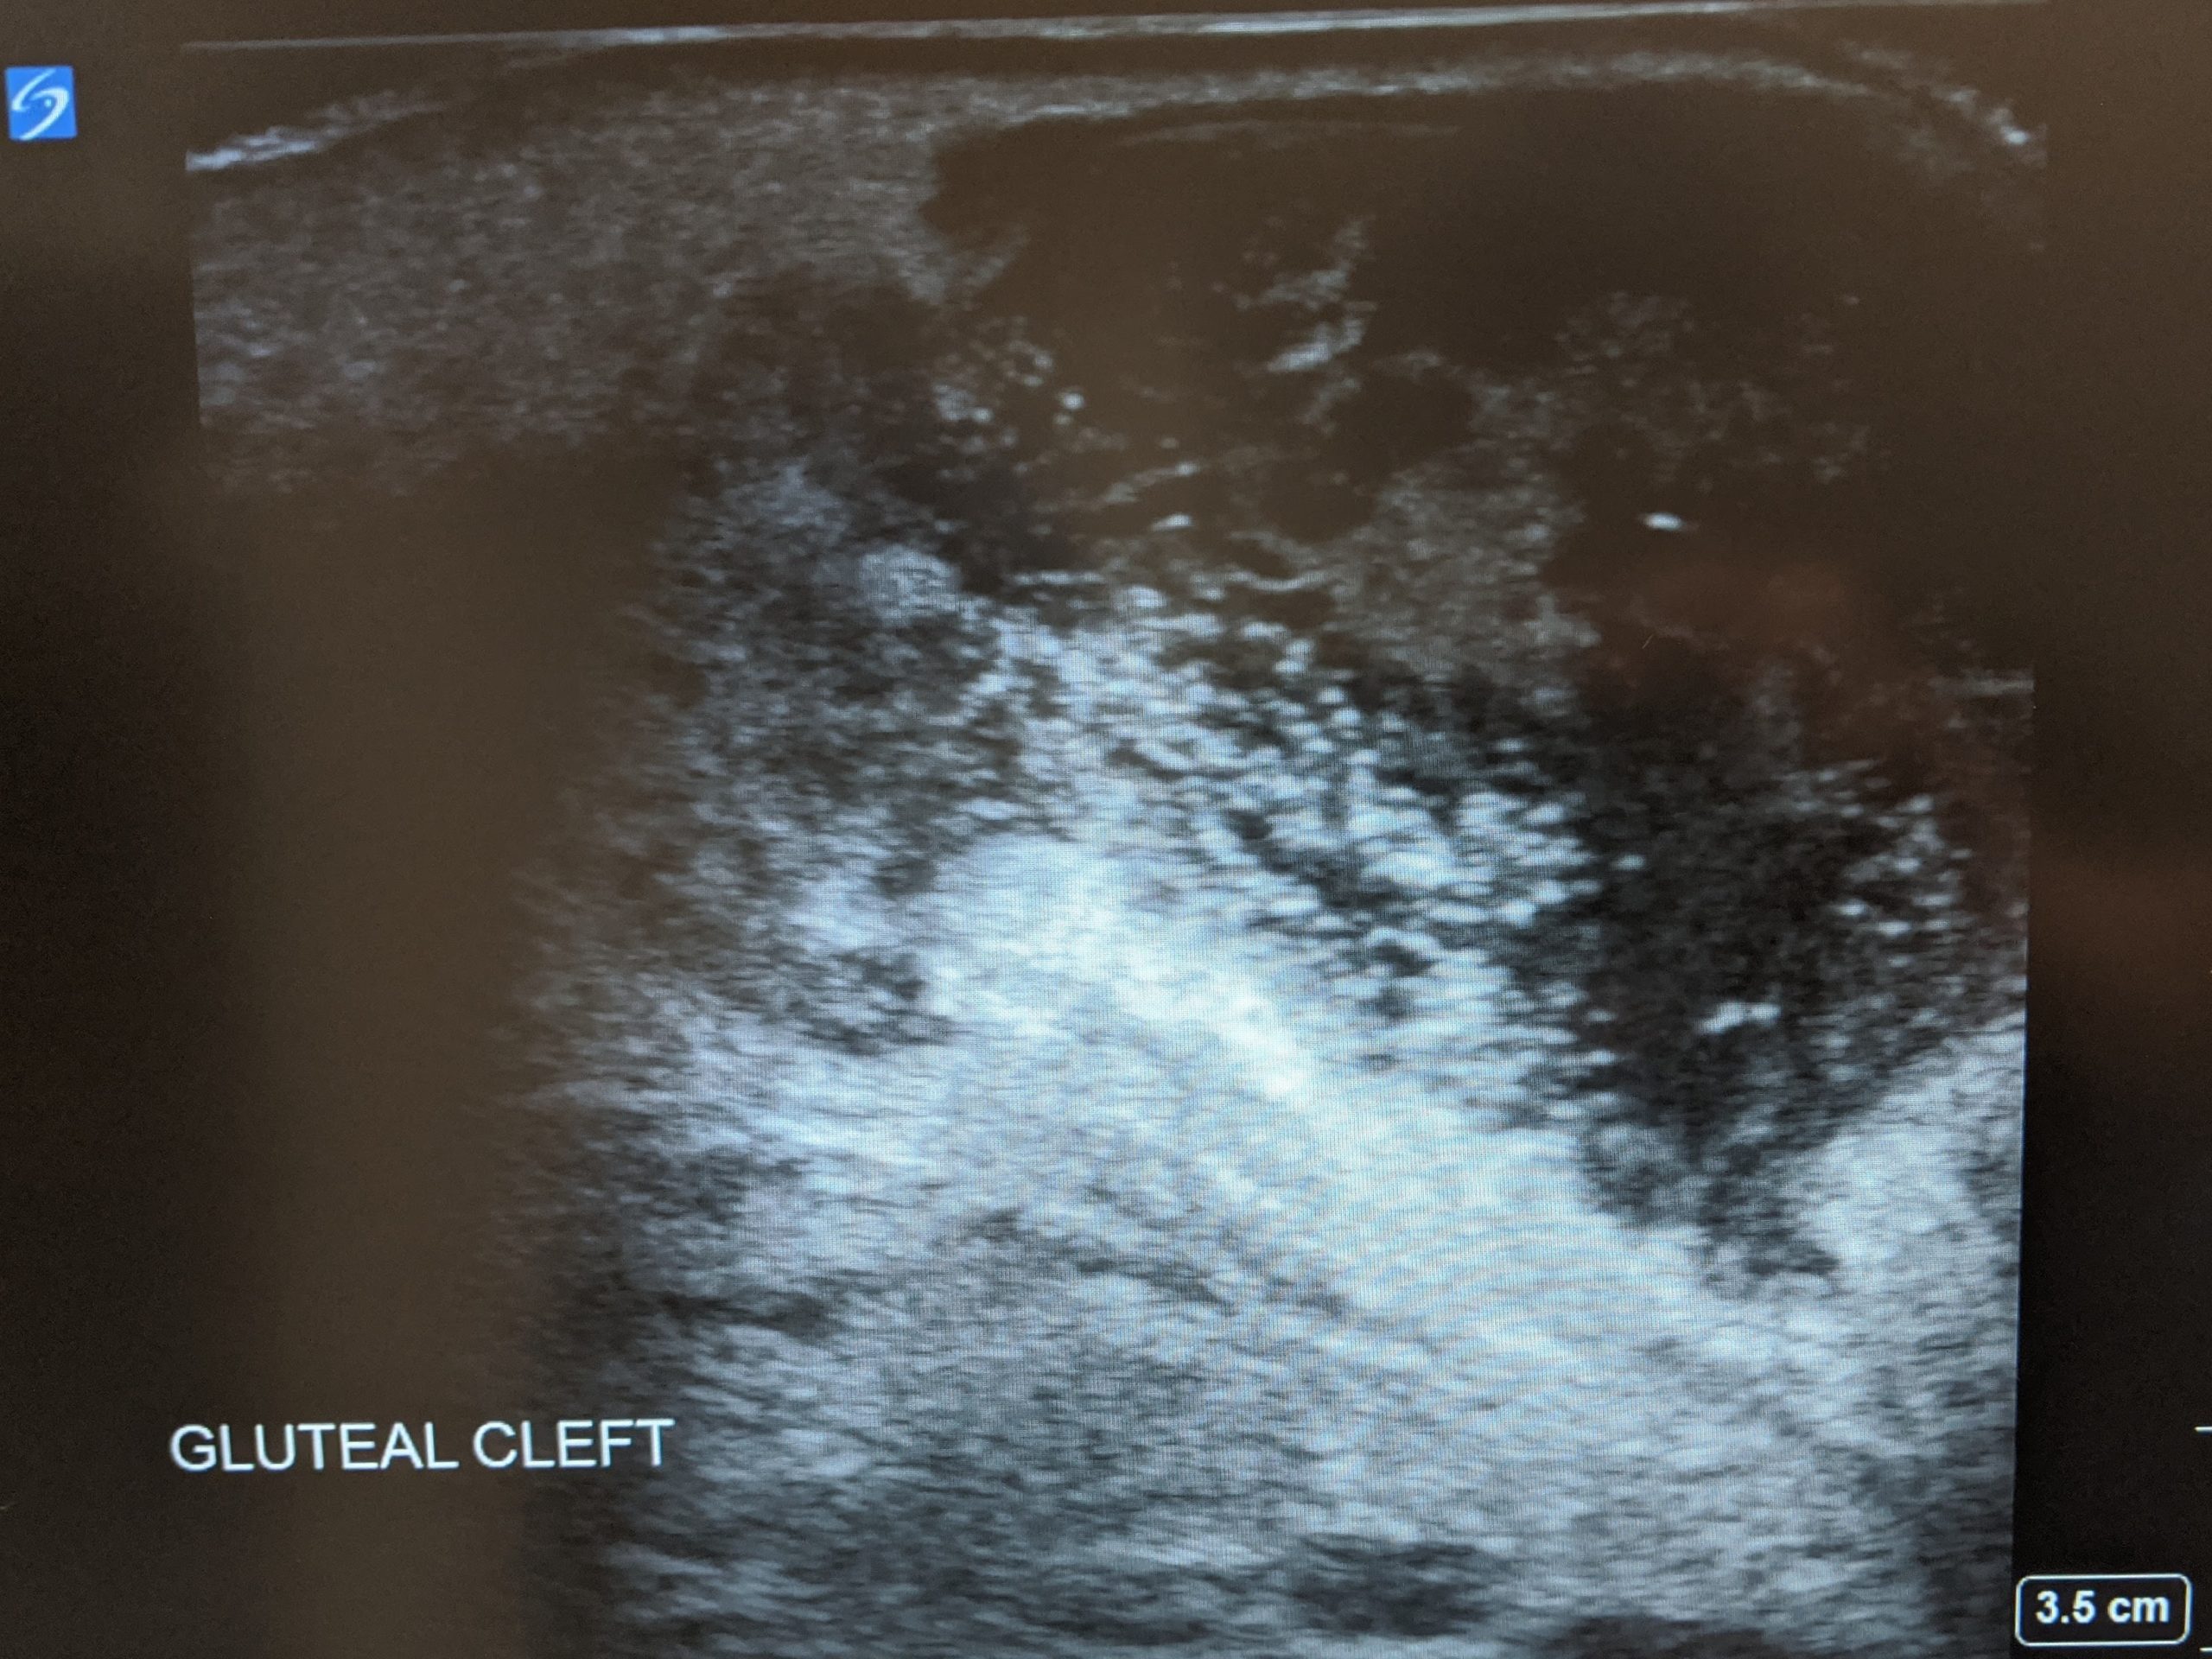

Pilonidal Cyst